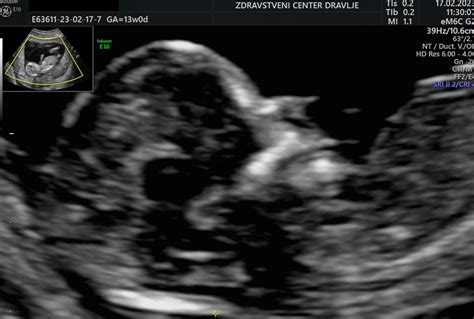

Nuhalna svetlina, strokovno imenovana tudi merjenje debeline nuhalne svetline, je prostor, napolnjen s tekočino, ki se nahaja na vratu ploda, med hrbtenico in kožo zatilja. Ta tanka plast tekočine je ultrazvočno vidna med 11. in 14. tednom nosečnosti, natančneje med 11 tedni in 0 dnevi (ko je dolžina ploda 45 mm) ter 13 tedni in 6 dnevi (ko je dolžina ploda 84 mm). Povečana debelina nuhalne svetline je lahko namreč povezana s povečanim tveganjem za nekatere kromosomske nepravilnosti, kot so Downov sindrom (trisomija 21), Edwardsov sindrom (trisomija 18) in Patau sindrom (trisomija 13).

Pregled nuhalne svetline se običajno izvaja preko trebušne stene nosečnice (transabdominalni ultrazvok), le redko je potreben vaginalni ultrazvok (transvaginalni). Pred posegom je nosečnico praviloma prosijo, da izprazni mehur, kar omogoči boljšo vidljivost. Med pregledom ultrazvočna sonda omogoča opazovanje ploda v gibanju, ocenjuje se njegova velikost od vrha glavice do trtice, premer glavice, frekvenca srčnega utripa ter prisotnost in oblika nosne kosti. Nosna kost je namreč pomemben marker, saj je pri otrocih z Downovim sindromom pogosto odsotna ali prekratka.

Poleg meritve nuhalne svetline se med tem pregledom izvede tudi natančen ultrazvočni pregled zgodnje morfologije ploda. Ta vključuje oceno razvoja srca, glavice, možganskih struktur, želodčka, sečnega mehurja, okončin, hrbtenice ter preverjanje celovitosti trebušne stene in razvoja popkovnice. V določenih primerih je mogoče z manjšo stopnjo gotovosti napovedati tudi spol otroka.

Skeniranje nuhalne svetline - prvo trimesečje